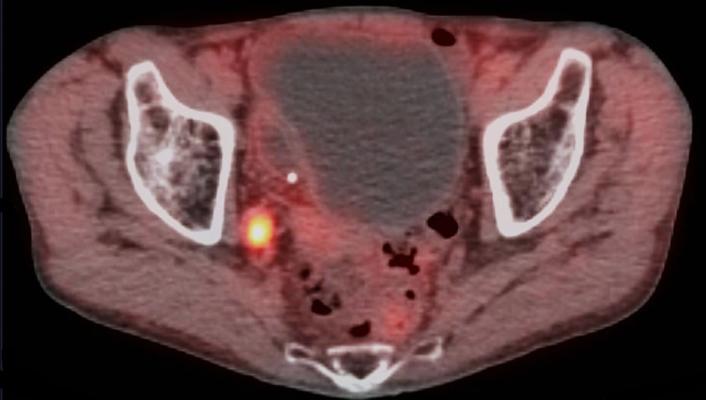

May 25, 2021 — Blue Earth Diagnostics, a Bracco company and recognized leader in the development and commercialization of innovative PET radiopharmaceuticals, is pleased to share news of the publication of a study from researchers at Winship Cancer Institute of Emory University (Winship) evaluating Axumin (fluciclovine F 18) PET imaging in men with recurrent prostate cancer. The randomized, prospective study showed that Axumin-guided post-prostatectomy radiation therapy increased biochemical event-free survival rates in men with recurrent disease. Among 165 patients whose prostate cancer had returned following surgical removal of their prostate, 75.5% whose treatment integrated Axumin PET imaging were event-free after three years, compared to 63% for whom only conventional imaging techniques were used to plan treatment. The increased event-free survival rate persisted after four years of follow-up, at 75.5% vs. 51.2%, respectively. Provider-reported genitourinary or gastrointestinal side effects were similar between the two study groups. Axumin, a novel amino acid-based radiopharmaceutical, is FDA-approved for PET imaging in men with suspected prostate cancer recurrence based on elevated blood prostate specific antigen (PSA) levels following prior treatment.

The manuscript, “EMPIRE-1: Randomized Trial Comparing Conventional- vs Conventional plus Fluciclovine (18F) PET/CT Imaging-Guided Post-Prostatectomy Radiotherapy for Prostate Cancer,” was published online in The Lancet on May 7, 2021 (DOI: https://doi.org/10.1016/S0140-6736(21)00581-X). The manuscript will also appear in an upcoming print issue. The EMPIRE-1 (Emory Molecular Prostate Imaging for Radiotherapy Enhancement) trial (NCT01666808) is the first randomized trial of men with recurrent prostate cancer to show that treatment based on advanced molecular imaging with 18F-fluciclovine PET can improve event-free survival rates. The Phase 2/3 trial was led by Winship radiation oncologist and prostate cancer specialist, Ashesh B. Jani, MD, MSEE, FASTRO, and Winship nuclear medicine specialist David M. Schuster, MD, FACR.

“The decision to offer post-prostatectomy radiation is complex, because conventional imaging can leave unanswered questions on the best approach for treatment planning,” said co-principal investigator Jani. “This research has found that integrating advanced PET imaging using 18F-fluciclovine into the treatment planning process allows us to do a better job of selecting patients for radiation therapy, guiding radiation decisions and planning, and ultimately, keeping our patients’ cancer under control. The group getting treatment guided by 18F-fluciclovine PET had a ‘cancer control rate’ of 75.5% at both three and four years; the group receiving treatment guided by conventional imaging had a ‘cancer control rate’ of 63% at three years and 51.2% at four years.”

“The question that we wanted to answer in this study was whether the treatment plan effect informed by 18F-fluciclovine PET imaging had a positive effect in the lives of patients,” said Schuster,. “The EMPIRE-1 trial allowed us to determine whether using 18F-fluciclovine PET imaging influences patient outcomes for the better, and the significant results confirm that it does."

The EMPIRE-1 (Emory Molecular Prostate Imaging for Radiotherapy Enhancement) trial (NCT01666808) study was a single-center-open-label, Phase 2/3, randomized controlled trial. It enrolled 165 patients (median age 61 years; inter-quartile range 55-68 years) whose cancer recurred after having undergone prostatectomies, but who later showed abnormal PSA blood test scores, indicating that their cancer had returned. All patients underwent conventional imaging (bone scan, CT or MRI) for initial treatment planning. Patients were then randomized 1:1 into two groups: the first receiving radiation therapy based on the initial treatment plans; the second receiving 18F-fluciclovine PET scans with treatment re-evaluated based on those findings. After three years, the study showed patients who were treated based on incorporating the 18F-fluciclovine PET imaging results had a higher event*-free survival rate (p=0.003), which persisted after four years (75.5% in the 18F-fluciclovine PET imaging arm, versus 51.2% in the conventional arm; p<0.0001). Provider-reported genitourinary or gastrointestinal side effects were similar between the two study groups.